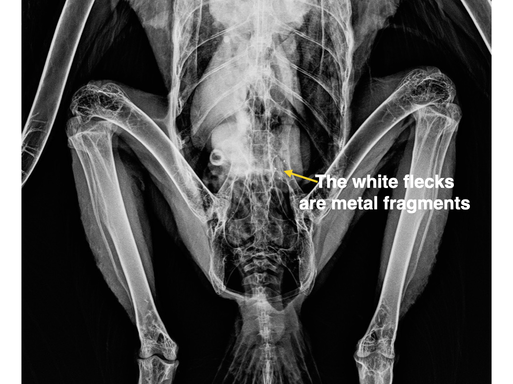

BMW continues to be busier than normal for the time of year. In 2021 there were 7 admissions by January 16. To date in 2022 there have been 25 admissions, 9 this past week: a Ruby-crowned Kinglet, a Northern Flicker, a Snow Goose (see photo above) and 6 raptors, including a Bald Eagle who died before reaching the clinic. We received permission to necropsy the eagle and another eagle who died last week. Necropsy results indicate that both eagles died from lead poisoning.

The radiograph below shows traces of lead in the digestive tract of the eagle. It was found near Paterson WA and died of lead poisoning before reaching the clinic.